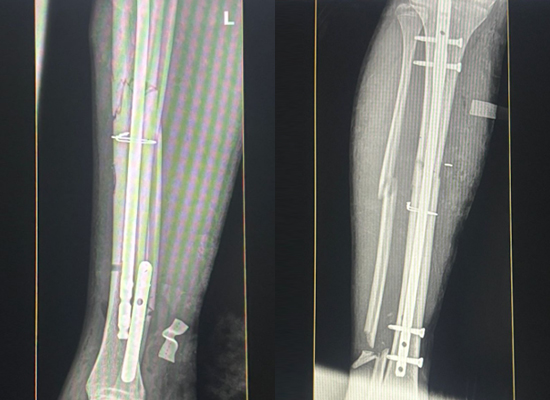

Preoperative imaging revealed a midshaft tibial fracture with mild displacement. A hybrid fixation technique (nail + plate) was selected to enhance mechanical strength and promote safe recovery.

Preoperative X-ray of tibial fracture

Postoperative Imaging

Postoperative radiographs showed excellent alignment and fixation integrity. The patient began gentle rehabilitation within weeks and achieved pain-free walking soon after.

Postoperative X-ray showing healing